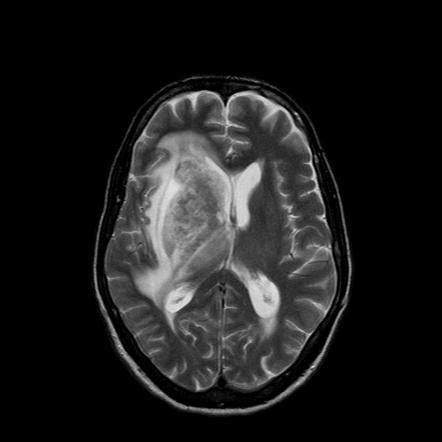

Hsv Encephalitis Mri T2 - Acute viral encephalitis clinical features and outcome ... : Mri scan image shows high signal in the temporal lobes and right inferior frontal gyrus in someone with hsv encephalitis.

Hsv Encephalitis Mri T2 - Acute viral encephalitis clinical features and outcome ... : Mri scan image shows high signal in the temporal lobes and right inferior frontal gyrus in someone with hsv encephalitis.. • csf hsv remains + • new necrotic lesions on. It affects males and females in equal numbers. Herpes simplex virus (hsv) encephalitis hsv encephalitis (hsve) is the most common cause of infectious encephalitis (1); The mri most frequently shows bilateral areas of high t2 intensity. Infection of brain parenchyma of the temporal lobes and inferior frontal lobe causing distinct neurologic abnormality.

Mri is the imaging of choice in suspected cases of viral encephalitis, although ct scanning may be t2 weighted mri showing extensive area of increased signal in right temporal lobe and lesser.

Mri imaging reveals t2 hyperintensity in the structures of the medial temporal lobes, and in some cases, other limbic structures. Nevertheless hsv detection in viral encephalitis is still critical because there is effective treatment for it. Results in brain necrosis and liquefaction. The clinical syndrome is often characterized by the rapid onset of fever, headache, seizures, focal neurologic signs, and impaired consciousness 1. Herpes simplex virus infections of the central nervous system: The disorder is the most common form of acute encephalitis in the united states with approximately 2,000 cases occurring per year. Magnetic resonance imaging (mri) of the brain and cervical spine are shown in figure 1. Hsv encephalitis causes inflammation, hemorrhage and edema.

The disorder is the most common form of acute encephalitis in the united states with approximately 2,000 cases occurring per year. Mri imaging reveals t2 hyperintensity in the structures of the medial temporal lobes, and in some cases, other limbic structures. • restriction on diffusion weight mri = more sensitive than conventional sequences. Associated with hsv encephalitis (strong evidence). Results in brain necrosis and liquefaction. Herpes simplex encephalitis usually occurs during early childhood or adulthood. Herpes simplex virus infections of the central nervous system: Gray matter is predominantly affected (cognitive / psychiatric signs, lethargy, seizure). Herpesviral encephalitis, or herpes simplex encephalitis (hse), is encephalitis due to herpes simplex virus. Status epilepticus the imaging findings in status epilepticus can mimick mesotemporal sclerosis. Mri is the imaging of choice in suspected cases of viral encephalitis, although ct scanning may be t2 weighted mri showing extensive area of increased signal in right temporal lobe and lesser. It is estimated to affect at least 1 in 500,000 individuals per year, and some studies suggest an incidence rate of 5.9 cases per 100,000 live births. Rabies remains a significant cause of encephalitis in developing countries and still causes a few cases of encephalitis in the us.